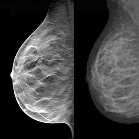

ماموگرافی ممکن است مرگ ناشی از سرطان پستان را به نصف کاهش دهد

علی‌رغم تردیدهای گذشته دربارة نقش مثبت ماموگرافی بررسی‌های جدید که توسط پزشکان آلمانی انجام شده است نشان داده‌اند که ماموگرافی می‌تواند مرگ ناشی از سرطان پستان در زنان 75-50 ساله را به نصف کاهش دهد ادامه>>